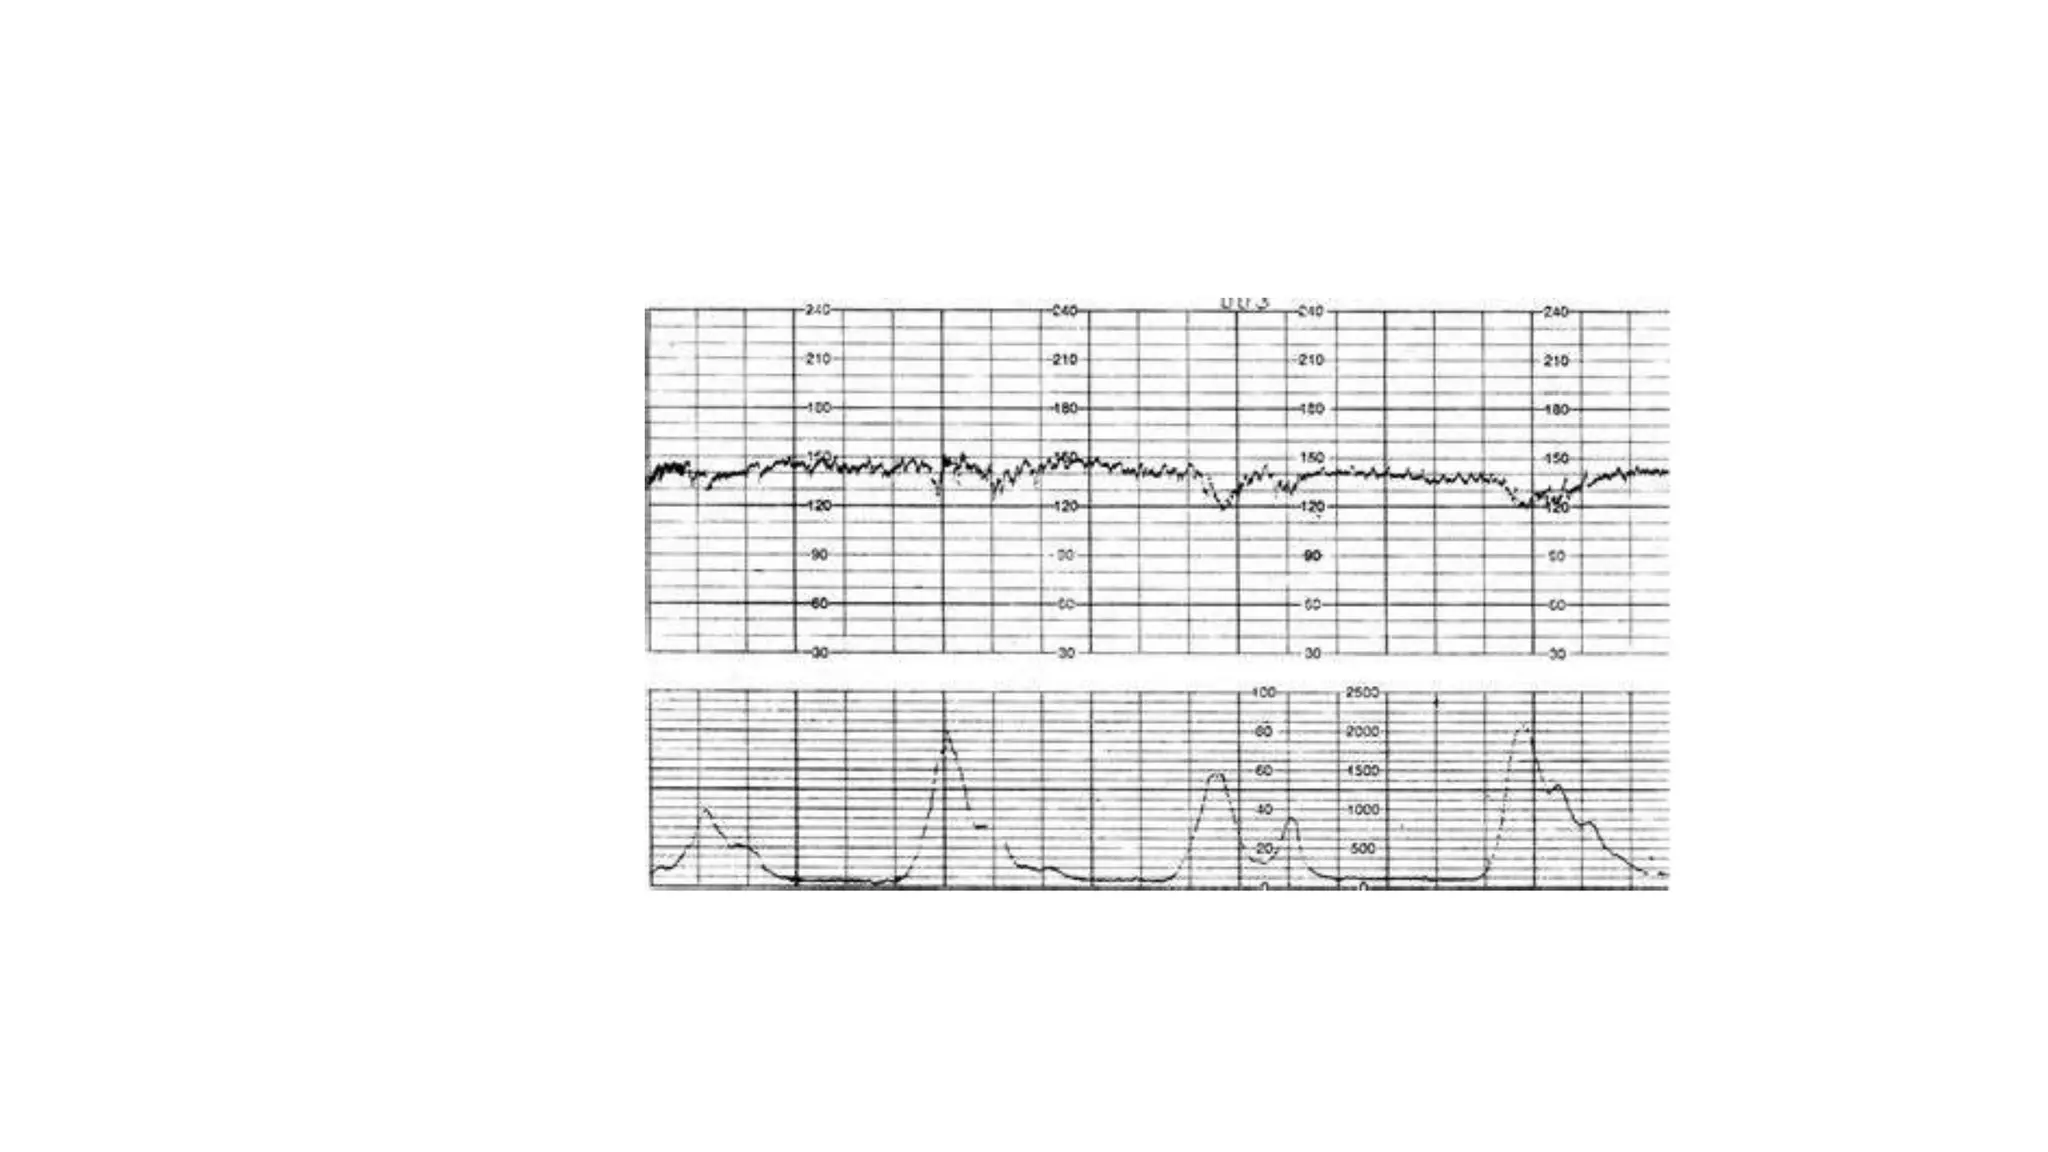

The document discusses key metrics for monitoring a baby's heart rate in utero, including the normal baseline rate of 100-160 bpm and variability. It also covers types of accelerations and decelerations that can occur, such as early or late, as well as bradycardia, which is an abnormally slow heart rate.